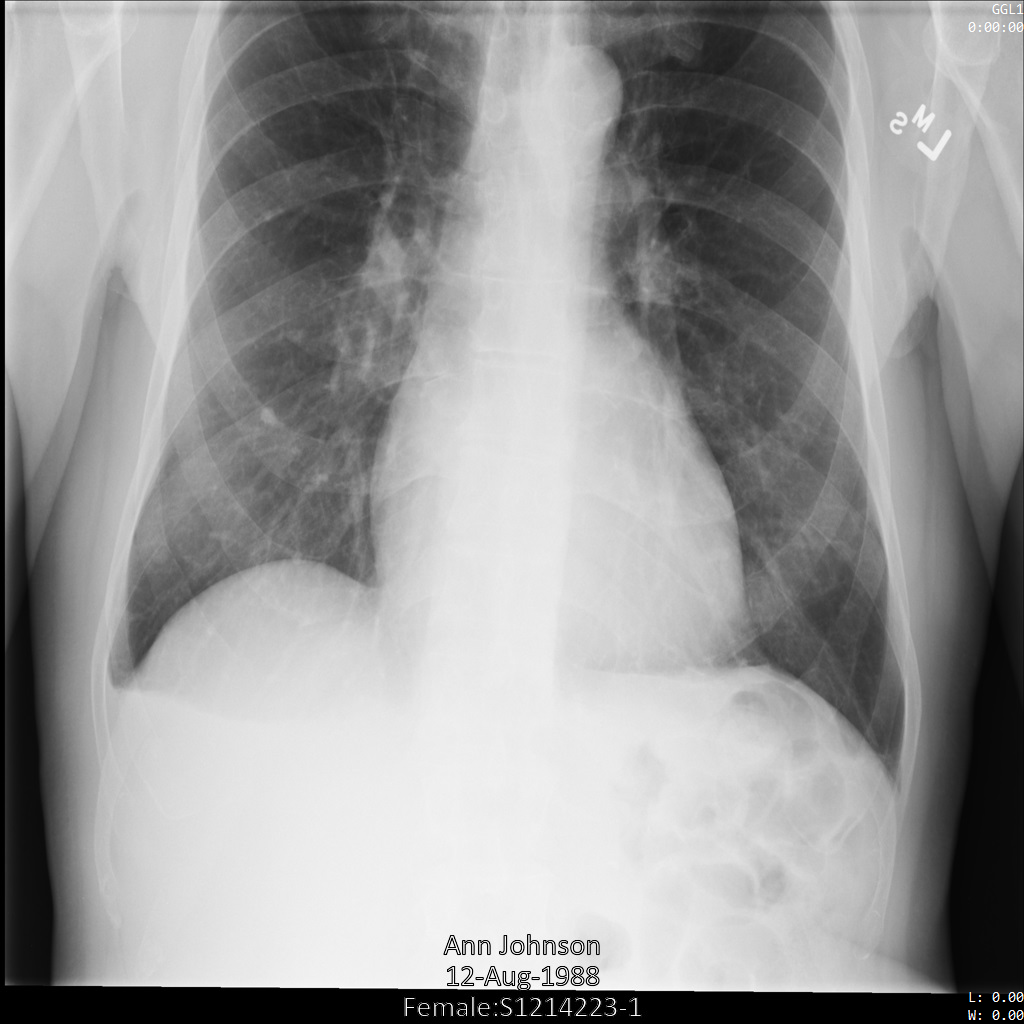

L'image suivante montre une radiographie non masquée d'un patient :

Une fois l'image envoyée à l'API Cloud Healthcare à l'aide de l'option REDACT_SENSITIVE_TEXT, elle apparaît comme suit :

Vous pouvez constater que les événements suivants se sont produits :

- Le paramètre

PERSON_NAMEen bas à gauche de l'image a été masqué. - Le paramètre

DATEen bas à gauche de l'image a été masqué.

Le sexe du patient n'a pas été masqué, car il n'est pas considéré comme du texte sensible selon le paramètre infoTypes DICOM par défaut.